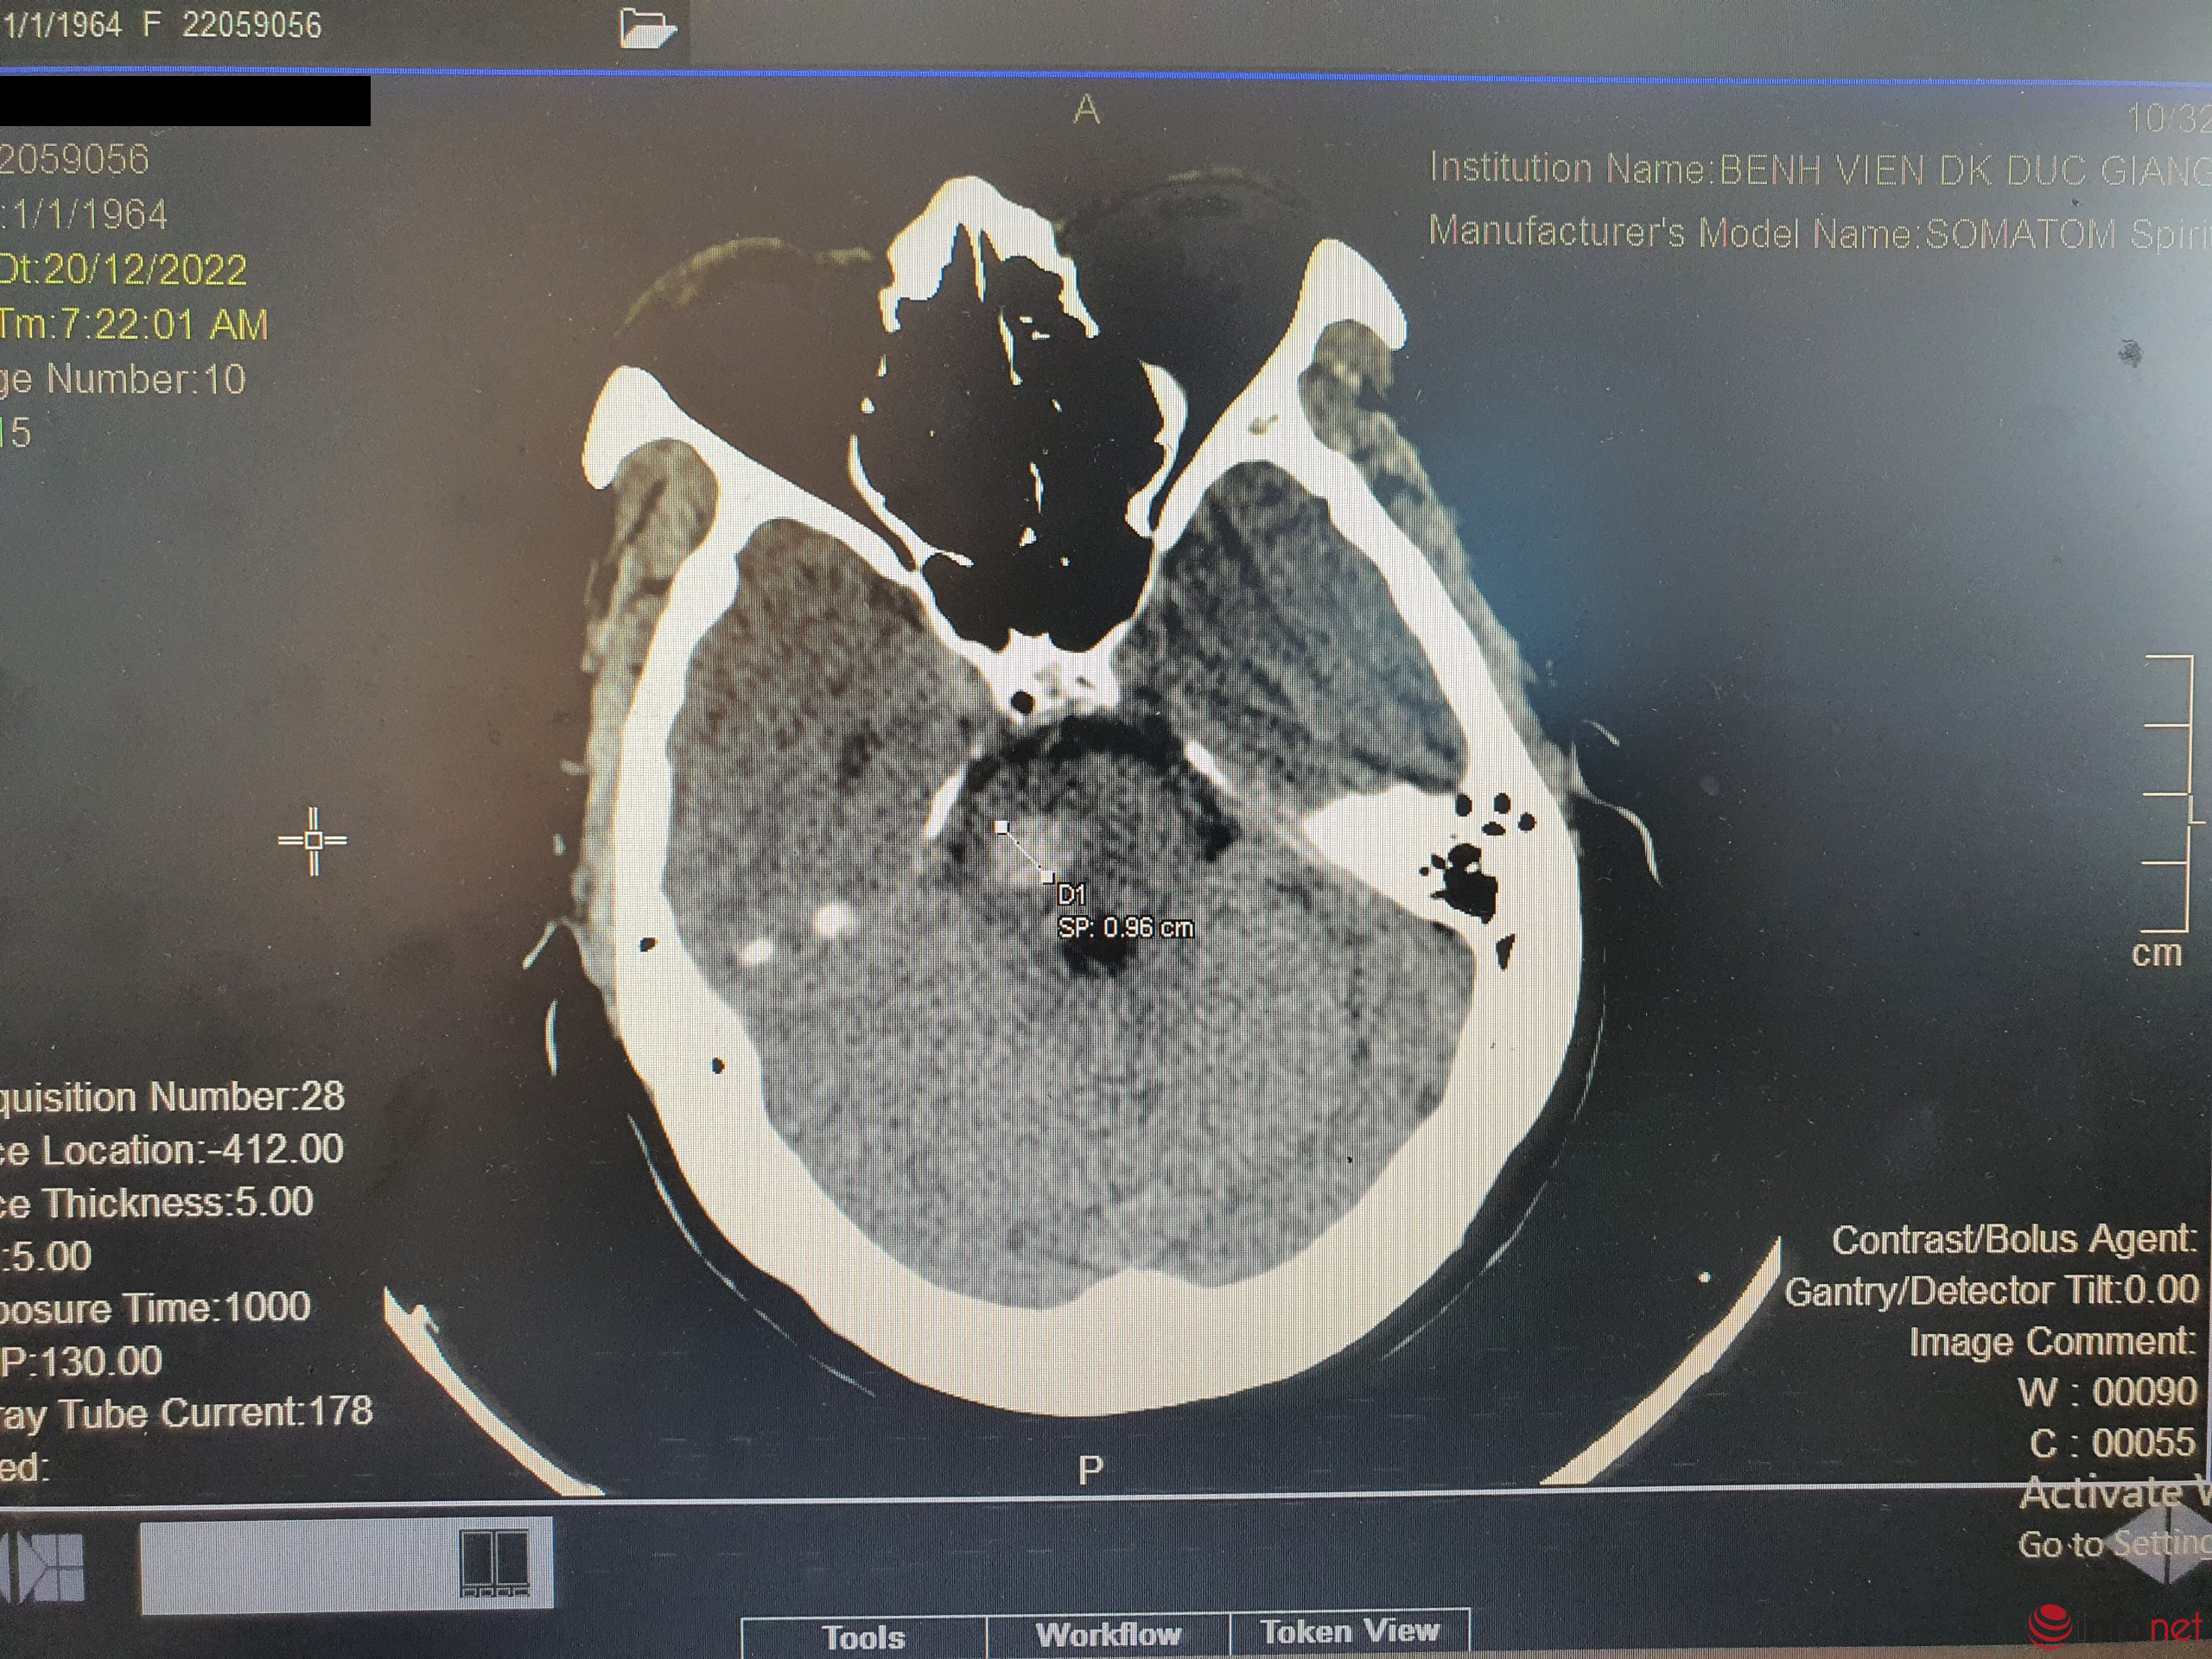

Bệnh nhân ngay lập tức được các bác sĩ đánh giá và chụp phim cắt lớp sọ não, chẩn đoán nhanh chóng được đưa ra là xuất huyết cầu não. Bà T. ngay lập tức được chuyển đến đơn nguyên điều trị đột quỵ để tiến hành các can thiệp cần thiết.